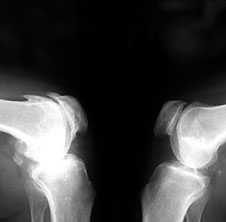

3. Заострение краев суставных поверхностей мыщелков бедренной и большеберцовой кости, чаще в медиальном отделе сустава (связано с большей нагрузкой на этот отдел сустава), особенно при наличии варусной деформации сустава; реже – в латеральной части или одновременно в обеих половинах суставной поверхности (рис. 2).

Рис. 2. Rо-графия коленных суставов в боковой проекции.

Артроз феморопателлярных суставов (больше слева). Артроз коленных суставов (I ст по Kollgren справа, IV ст. по Kollgren слева)